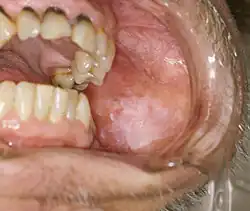

Leukoplakia (rogowacenie białe, łac. leukoplakia) – zmiana przedrakowa[1] w obrębie błony śluzowej najczęściej jamy ustnej charakteryzująca się obecnością białych plam lub smug na powierzchni błony śluzowej. Ścisła definicja WHO określa leukoplakię następująco: określenie kliniczne do opisu białych plam o niejasnym ryzyku, wtedy gdy inne specyficzne choroby, jednostki i zmiany przednowotworowe zostały wykluczone[2].

Makroskopowo obserwuje się białawe, gładkie lub szorstkie, matowe, dobrze odgraniczone zgrubienie na błonie śluzowej czerwieni wargi dolnej, policzka lub podniebienia. Podział kliniczny jest na zmiany homogenne (jednorodne, zwykle mikroskopowo bez obserwowanej dysplazji nabłonka) oraz niehomogenne (niejednorodne, zwykle dysplazja jest obserwowana).

Zmiany mogą być pojedyncze lub wieloogniskowe, a nawet rozlane. Najczęściej występują u starszych mężczyzn w piątej-siódmej dekadzie życia. 3-6% zmian transformuje w raka płaskonabłonkowego. Zmiany o podobnym charakterze dotyczyć mogą niekiedy narządów płciowych – skóry prącia, sromu i szyjki macicy.